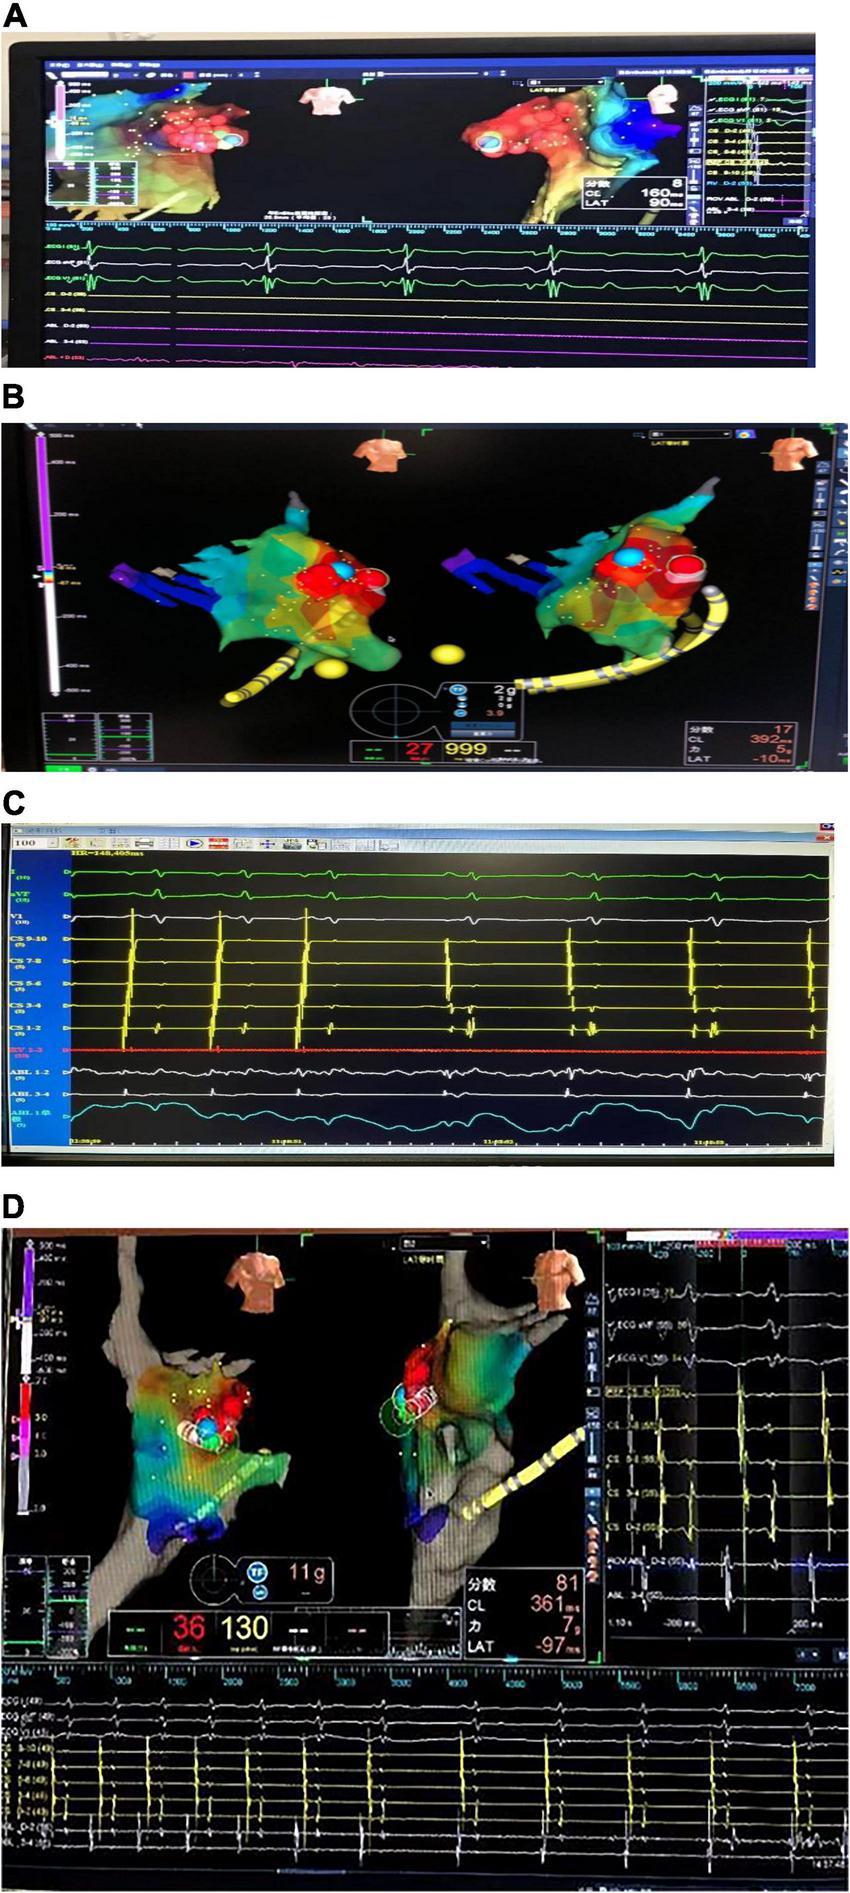

Three children with AT from the AA were treated by RFCA. In case 1, the earliest excitation point was marked at the peak of RAA during the operation. The catheter was perfused with cold saline, and the ablation parameters (43°, 35 W, 17 ml/min) were selected, and the pressure was controlled at 5–10 g. Atrial tachycardia was terminated after acceleration, and consolidation ablation was performed four times for 60 s. Atrial tachycardia could not be induced by regular atrial programed stimulation or atrial programed stimulation following intravenous isoprenaline drip. In case 2, the A wave at the apex of the LAA occurred earliest during the operation. The catheter was perfused with cold saline, and the ablation parameters (43°, 20–30 W, 17 ml/min) were selected, with the pressure controlled at 5 g. Atrial tachycardia converted to sinus rhythm temporarily but returned to AT after a few seconds. Sinus rhythm and AT appeared alternately in the child after 40 s × 5 times consolidation ablation around this area. Because the best target was located at the apex of the LAA and the ablation risk was high, resection of the LAA was performed through the posterior lateral incision of the left chest combined with cardiothoracic surgery. In case 3, meticulous mapping was performed from outside to inside along the RAA. The earliest excitation point was marked at the tip of the middle part of the RAA, the ablation parameters (43°, 25–35 W, 17 ml/min) were selected, and the pressure was controlled around 5–10 g. Atrial tachycardia was terminated after acceleration, and consolidation ablation was performed for 60 s. After the operation, AT recurred, and thoracoscopic RAA resection was performed in combination with cardiothoracic surgery. During the atrial appendectomy, ECG monitoring suggested that atrial tachycardia was terminated after the atrial appendage was clamped. Figure 2 shows three-dimensional mapping shown in, and Figure 3 shows postoperative pathology.

FIGURE 2

Three-dimensional electroanatomical mapping. (A) Three-dimensional electroanatomical mapping of case 1 showed the atrial tachycardia (AT) from right atrial appendage (RAA): the earliest excitation point in the red area is the RAA, the red circle is the ablation target, and the blue circle is the best ablation target. (B) Three-dimensional electroanatomical mapping of case 2 showed the AT from left atrial appendage (LAA): the earliest excitation point in the red area is LAA, the red circle is the ablation target, and the blue circle is the best ablation target. (C) The electrogram of the target site of case 2: during the ablation, the atrial activation sequence was changed from CS1-2 to CS9-10 to CS9-10 to CS1-2. (D) Three-dimensional electroanatomical mapping of case 3 showed the AT from RAA: the earliest excitation point in the red area is the RAA, the red circle is the ablation target, and the blue circle is the best ablation target. The sequence of atrial activation did not change significantly, but the shape of the A wave and the AA interval was changed. AT, atrial tachycardia; LAA, left atrial appendage; RAA, right atrial appendage.